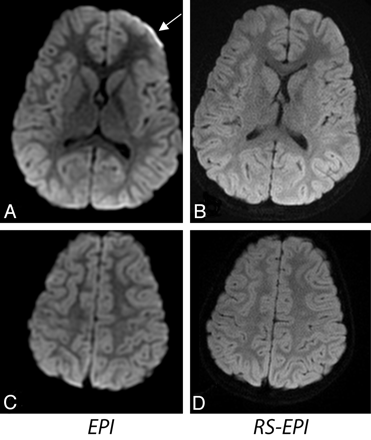

The average scores calculated across 35 patients are shown in Fig 2. The following scores were given to EPI, RS-EPI, and RS-EPI re-evaluated alongside the EPI, respectively: resolution, 3.5/5.8/5.2; distortion level, 2.9/5.5/6.0; SNR, 3.4/4.2/4.1; lesion conspicuity, 3.3/6.0/5.9; and diagnostic confidence, 3.2/5.8/6.0. The P values for EPI versus RS-EPI viewed first independently and then as a direct comparison, were as follows: resolution, 1.9 × 10−6/1.2 × 10−6; distortion level, 1.3 × 10−6/9.5 × 10−7; SNR, .006/.007; lesion conspicuity, .005/.007; and diagnostic confidence, 1.3 × 10−6/1.9 × 10−6. Overall, the RS-EPI had significantly improved diagnostic confidence. RS-EPI identified a lesion not found by EPI in 1 patient (a small subdural empyema, Fig 3) and more accurately defined the extent and location of the lesions, such as ischemic injury, metabolic disorder (Fig 4), a cystic encephalomalacia (Fig 5), and a skull base tumor. In 1 case, RS-EPI (Fig 6B) correctly identified a false-positive ischemic lesion in the temporal lobe seen on EPI in a patient with Moyamoya disease (Fig 6A). In another case, RS-EPI (Fig 6D) correctly identified a false-negative ischemic lesion in the temporal lobe in a postoperative patient with Moyamoya disease, where this was presumed to be a post-operative blood-product artifact on EPI. (Fig 6C).

Two patients with Moyamoya disease. A and B, An 8-year-old girl presenting with possible infarct or blood product at the surgical site on EPI (solid white arrow). The absence of these distortion artifacts on RS-EPI makes this confidently negative. The open white arrows indicate undesirable brightening of the flocculus due to susceptibility artifacts from the brain/bone interface. C and D, A 3-year-old boy presenting with possible postoperative blood-product artifacts on EPI (white arrow), but the lesion appears more suspicious for an ischemic lesion on RS-EPI. On closer inspection, the lesion demonstrates subtle cortical T2 high intensity on the T2 FSE sequence, confirming the suspicion that this represents a true ischemic focus, rather than distortion related to postoperative changes. These 2 cases demonstrate that RS-EPI is both sensitive and specific.